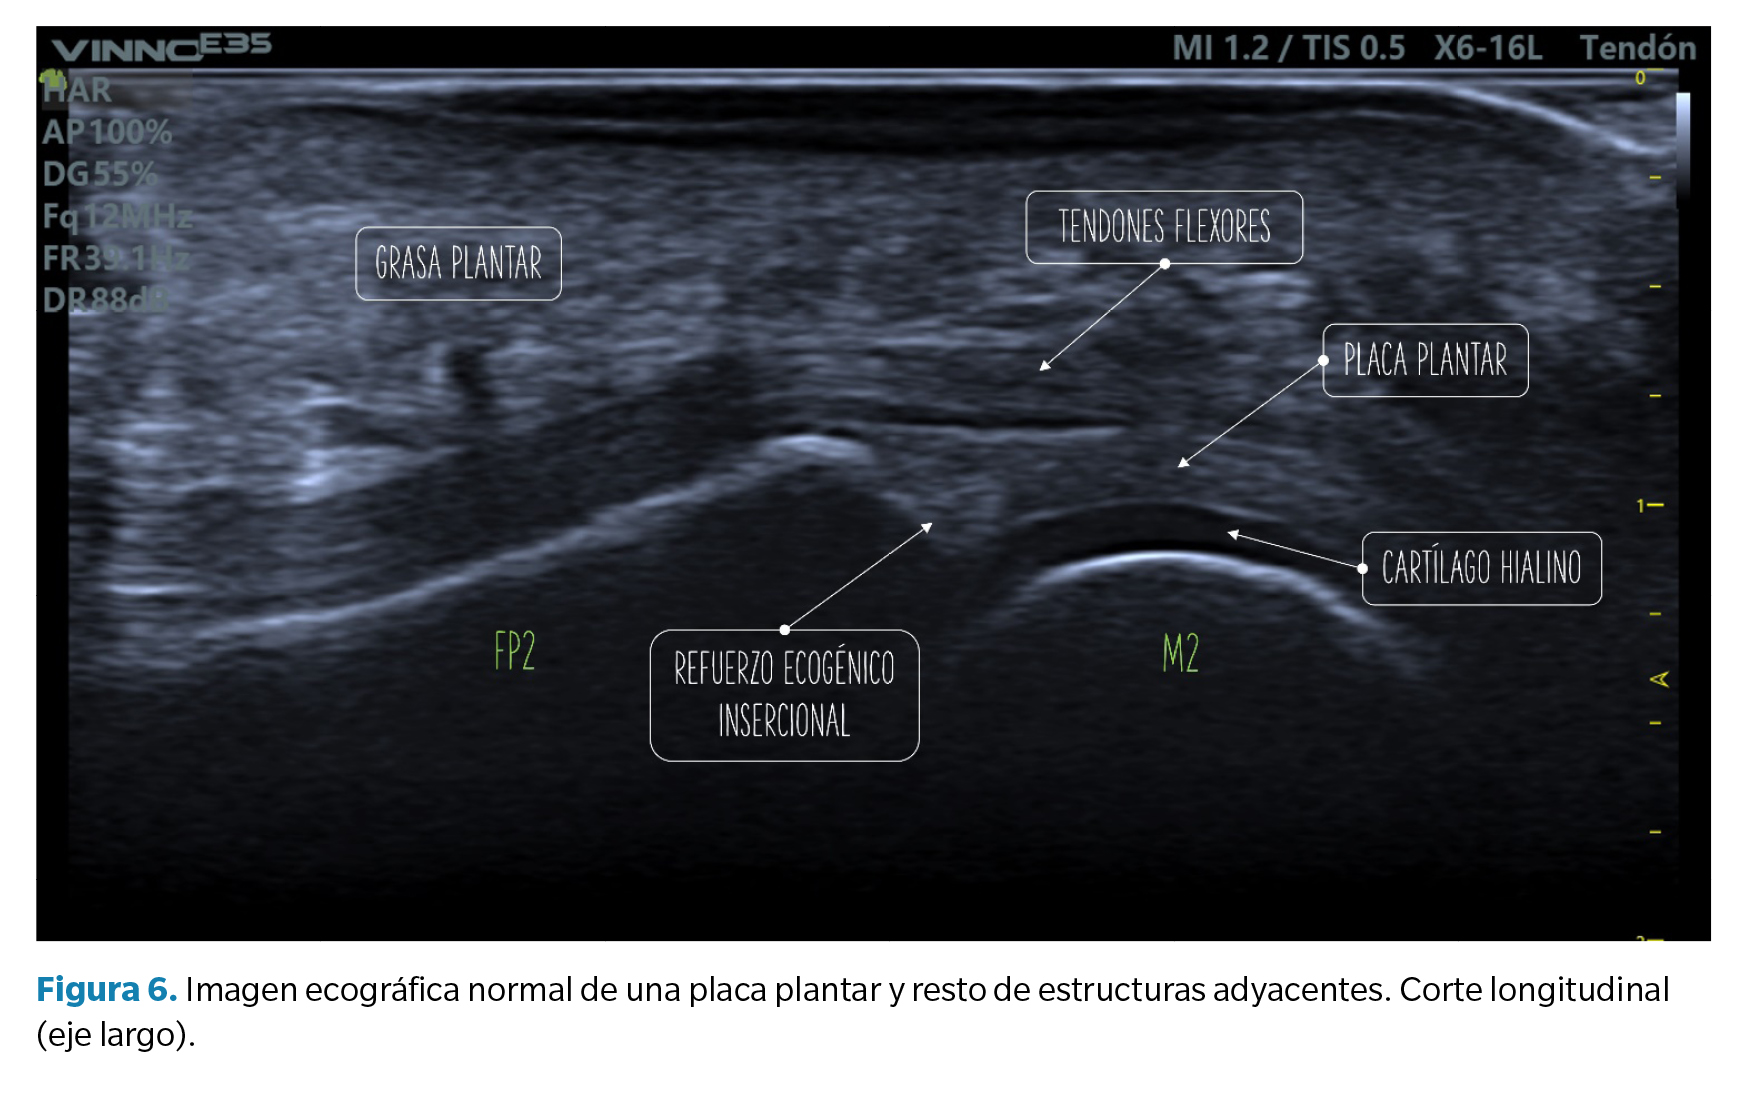

Criterios de normalidad de la imagen ecográfica

• Corte longitudinal (eje largo): la placa plantar normal se muestra ecográficamente como una estructura curvilínea ligeramente ecogénica con ecotextura granulada homogénea. Esta textura permite la diferenciación, no siempre definida, con los tendones flexores subyacentes de textura fibrilar. La superficie articular de la placa se define con precisión limitando con el cartílago hialino de la cabeza metatarsal, hipoecoico (Figura 6).

En la unión con la falange proximal, bien definida, el contorno óseo es normalmente liso y en la placa puede aparecer una zona triangular más ecogénica que se ha descrito como un hallazgo ecográfico normal y podría representar una mayor proporción de fibras de colágeno. La unión proximal al cuello metatarsal, en cambio, tiene una definición pobre en imagen ecográfica (Figura 6).